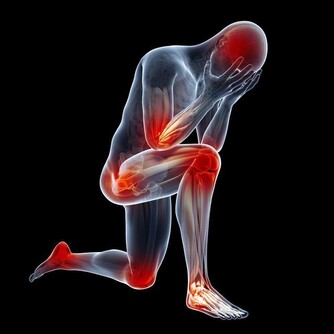

先說“痛”字,主要是發病時患者的關節會產生劇痛,就像身體的某個部位長出刺來一樣,想想就內心就覺得疼啊!再說“風”,這說明痛風也就是痛一會兒,時間不是很長,就像一陣風刮過之後,就沒了!